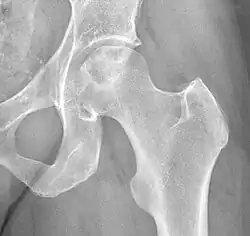

Chandler's disease, also known as idiopathic avascular osteonecrosis of the femoral head (ANFH or ONFH), is a rare condition in which the bone cells in the head of the femur (FH) die due to lack of blood. This disease is caused when blood flow is reduced to the part of a bone near a joint. It is specifically unique because the femoral head is for some reason the only affected part of the body and rarely travels down to the main part of the femur. In 1948, F. A. Chandler did a multi-case review and first released his interpretations as Coronary Disease of the Hip. This term is now considered incorrect as it improperly describes the actual disease.[1]

The current etiology or origin of this disease is unknown. Some studies theorized that bone remodeling is maintained in a microenvironment in the FH meaning that there is a greater local component to changes to the femoral head than the normal systemic way that bone remodeling is handled throughout the body. As a whole our body goes through bone remodeling using various hormones and glucocorticoids to balance the uptake and output of bone throughout the entire body. The local portion is considered to be controlled partially by inflammatory cells called cytokines and individual growth factors. The theory is that the local bone remodeling is malfunctioning and overpowering the systemic bone remodeling causing the FH to be highly susceptible to necrosis. Studies have determined that there are risk factors that are more than likely associated with the development of the disease but many of them are very broad and include large groups of people for example alcoholics, diabetics, and many other common core morbidities. Unfortunately, most are classified under idiopathic due to being unable to truly narrow down the origin of why it only happens to the head of the femur. What most clinicians observe is that the head of the femur seems to almost have a system of its own somewhat separate from the rest of the femur. There are many theories as to how the head of the femur dies unlike why it is happening.[3]

Trauma can be classified as a fracture or dislocation of the FH. This can lead to damage to the extraosseous or outer bone blood supply. This is especially prevalent to fractures in the junction between the FH and the neck of the femur called the sub capital region. Trauma at the sub capital region interrupts the connection or anastomosis between the outer blood vessels on the end of the bone or lateral epiphyseal vessels causing poor blood flow to the FH. Lastly, direct irradiation, chemotherapy, or oxidative stress may lead to cellular malfunction ultimately leading to cellular death.[2]